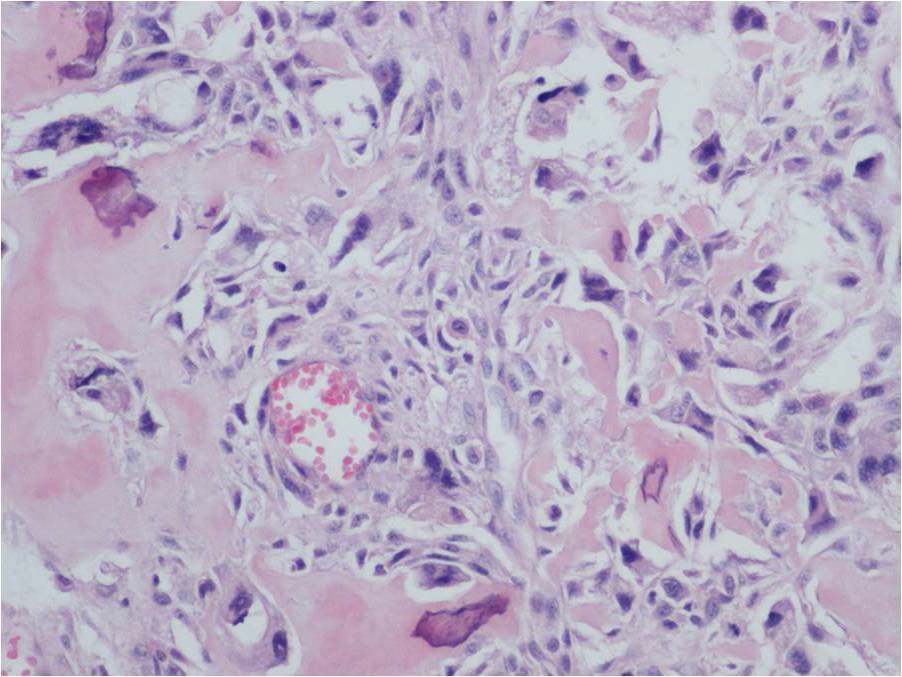

Extraskeletal osteosarcoma is generally a high-grade malignancy, similar to a high grade conventional intraosseous osteosarcoma. Microscopically, tumors usually have an infiltrative margin with occasional satellite nodules; however, on gross inspection they appear well defined. Tumor cells produce a variable amount of osteoid and bone (Fig. 8-10). Necrosis and hemorrhage are common. Five subtypes have been described similar to conventional osteosarcoma of bone: osteoblastic; chondroblastic; fibroblastic; telangiectatic; and small cell.

Fig. 8-10: Microscopic Pathology. Low (Fig. 8), intermediate (Fig. 9) and high (Fig. 10) power magnification H&E slides. Osteoid and bone formation produced by tumor cells, without interposition of cartilage. Tumor cells are crowded, disorganized, pleomorphic and darkly stained. There are mitotic figures.